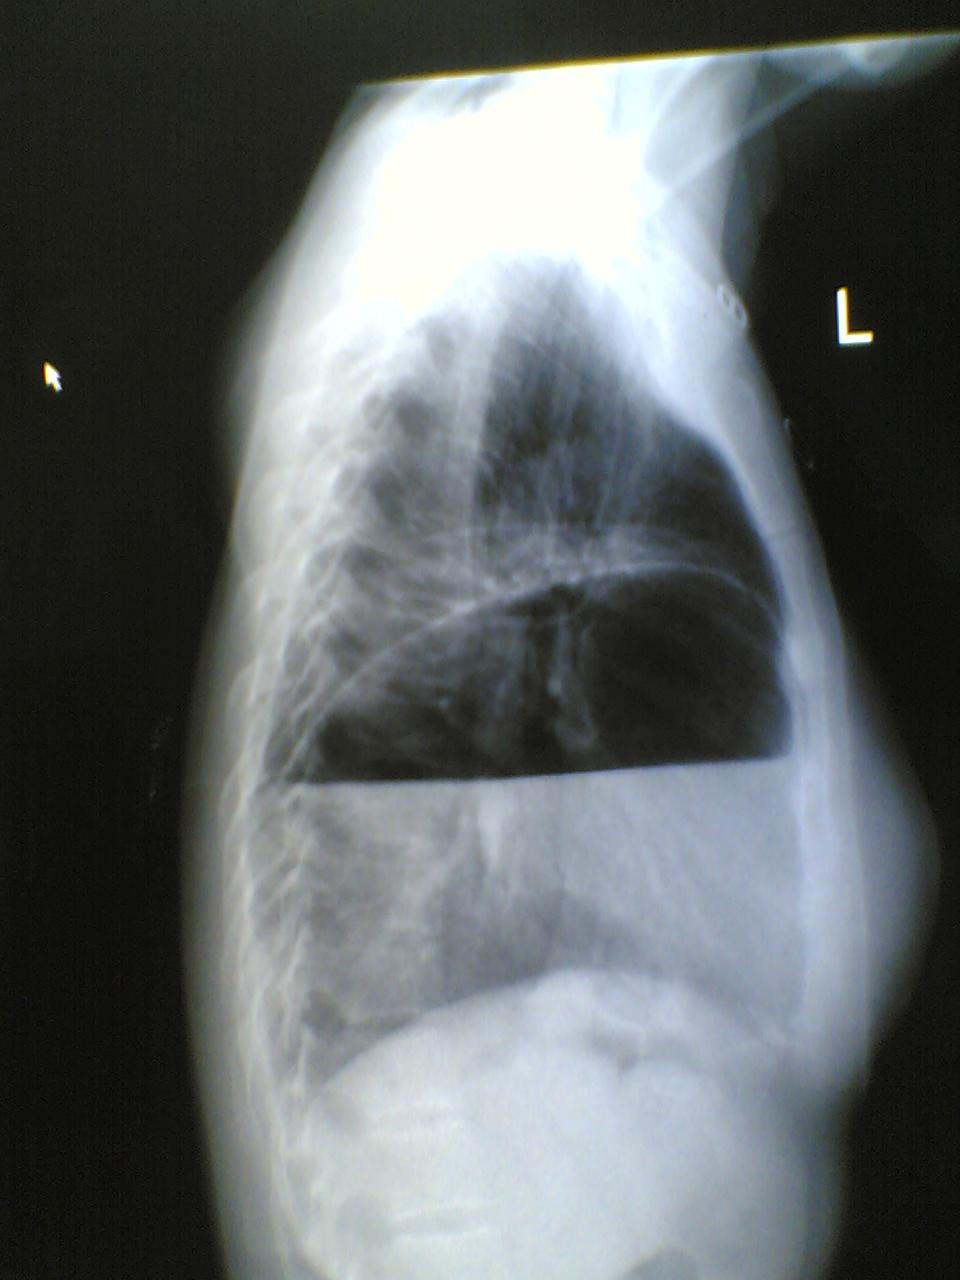

标题: X7060:女,40,呕吐一日,自觉上腹部不适,剑突下痛。 [打印本页]

标题: X7060:女,40,呕吐一日,自觉上腹部不适,剑突下痛。

膈疝?膈膨升?胃泡上是膈面还是肺组织?请各位老师多多指教(图像质量欠清,包涵)

1)考虑左侧膈疝。2)左下肺盘状肺不张。

左侧膈疝,伴胃扩张,左下肺膨涨不全(压缩所至)。

左侧膈疝,左下肺盘状不张。

1)考虑左侧膈疝。2)左下肺盘状肺不张。支持!应该做钡餐或透视进一步检查。